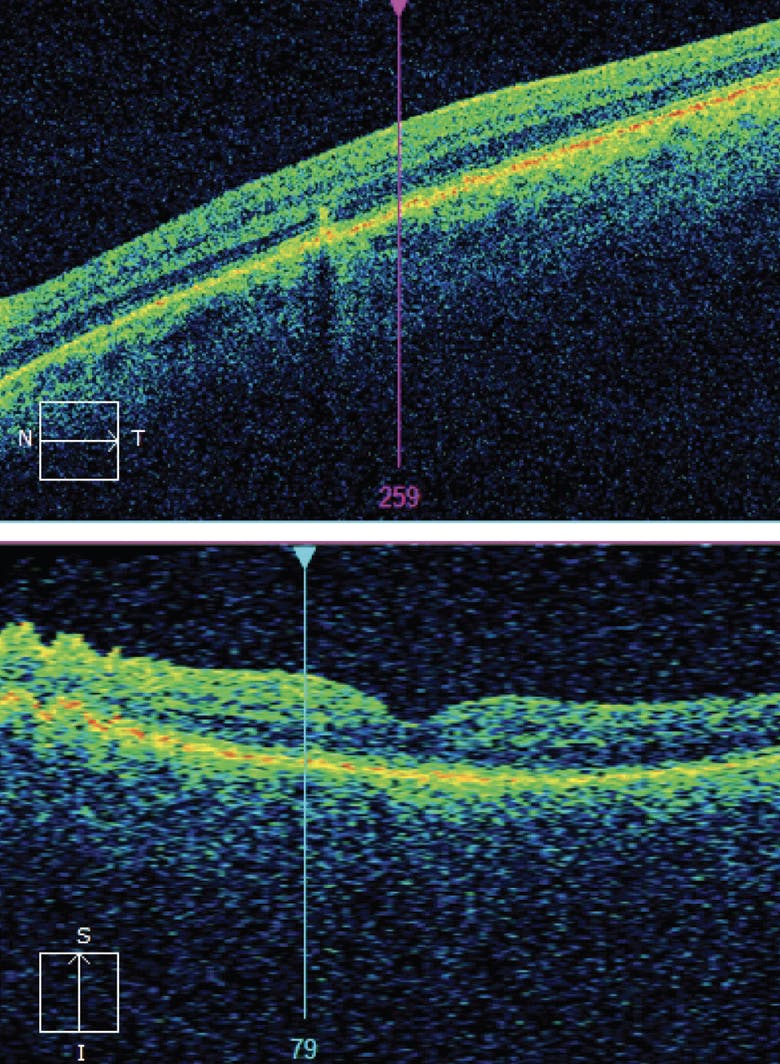

A 72-year-old man with long-standing wet AMD in the right eye (diagnosed in 2017) who had undergone previous treatment with anti-VEGF therapy with a disciform scar (Figure 1) was now being observed with VA of 20/800 OD and intermediate AMD in the left eye with VA of 20/25 (Figure 2). Due to the high risk of conversion to wet AMD in the left eye and the monocular status, the patient was referred for at-home monitoring with the ForeseeHome AMD Monitoring Program (Notal Vision). The patient began using the device in July 2018 and was monitored in-office every 6 months.

<p>Figure 1. At presentation, the patient’s right eye had wet AMD, a disciform scar, and VA of 20/800.</p>

Figure 1. At presentation, the patient’s right eye had wet AMD, a disciform scar, and VA of 20/800.

<p>Figure 2. At the time that the patient began at-home monitoring, his left eye had intermediate AMD with a VA of 20/25.</p>

Figure 2. At the time that the patient began at-home monitoring, his left eye had intermediate AMD with a VA of 20/25.